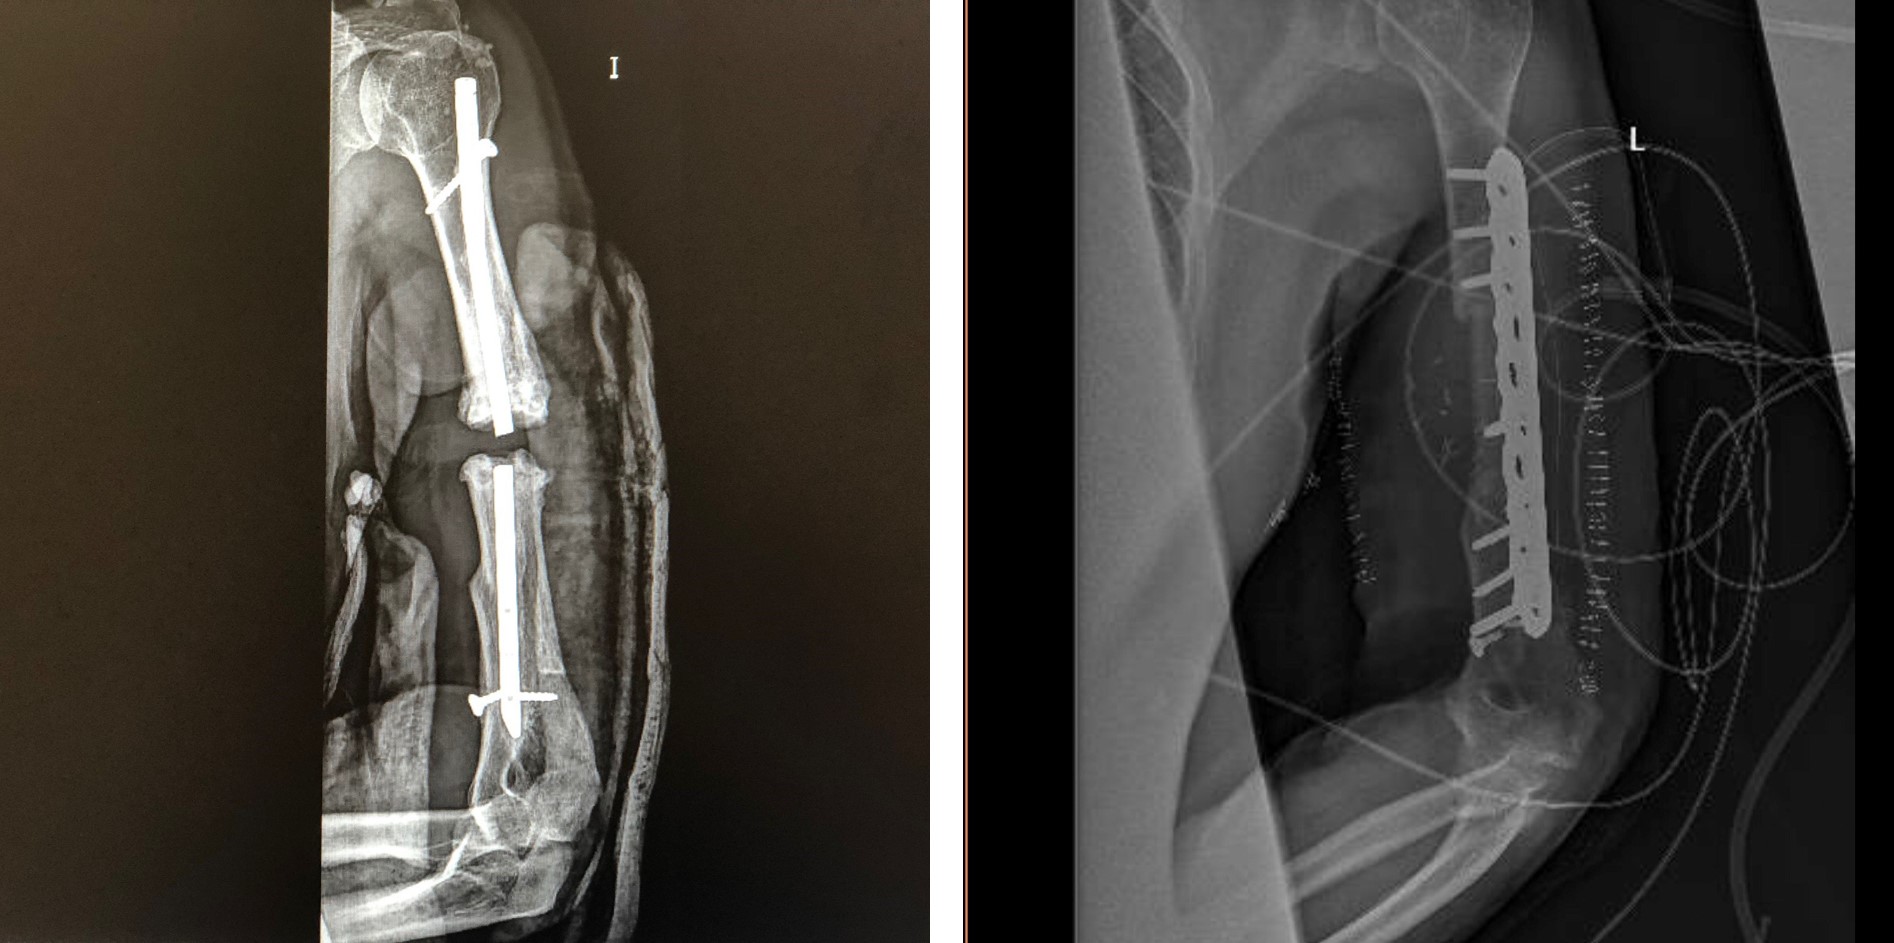

Gracias a todo ello, el Hospital Universitario General de Villalba pudo realizar recientemente una innovadora cirugía de reconstrucción, utilizando el modelo 3D y las guías de corte quirúrgico impresas en 3D, específicas y adaptadas a la anatomía del paciente, en un varón con fractura muy compleja del húmero como consecuencia de un accidente de tráfico hace diez años.

El paciente se había sometido a varias intervenciones en distintos centros hospitalarios, sin conseguir consolidación de los fragmentos óseos, y actualmente el hueso presentaba "pseudoartrosis" por falta de flujo sanguíneo, requiriendo resecar la parte del húmero afecto y aportar nuevo hueso sano. En este caso, el equipo quirúrgico liderado por el Dr. Alfonso Prada, especialista del el Servicio de Cirugía Ortopédica y Traumatología del hospital villalbino, en colaboración con el Servicio de Cirugía Oral y Maxilofacial de este centro y de los citados valdemoreño y mostolense, planteó un abordaje poco convencional para reconstruir el hueso.

"Realizamos un trasplante utilizando el peroné del propio paciente para adaptarlo al defecto previamente planificado de hueso humeral"; explica la Dra. Lorena Pingarrón, jefe del Servicio de Cirugía Maxilofacial, recordando la cirugía multidisciplinar en la que, junto a los doctores Paula Barba y Santos Crespo, especialistas del mismo servicio, "se adaptó a las necesidades que el Dr. Prada transmitió en su paciente para obtener, en conjunto, el mejor resultado funcional".

Gracias a la planificación milimétrica del defecto, el equipo de Planificación Quirúrgica 3D pudo diseñar las guías de corte del peroné y del húmero y realizar un estudio tridimensional junto con los cirujanos para acoplar el trasplante de hueso de la pierna al brazo. "La cirugía transcurrió sin complicaciones, con reducción considerable del tiempo quirúrgico con respecto a una intervención sin planificación tridimensional", concluyen los doctores Prada y Pingarrón, recordando que el paciente fue dado de alta a los 4 días de la operación.